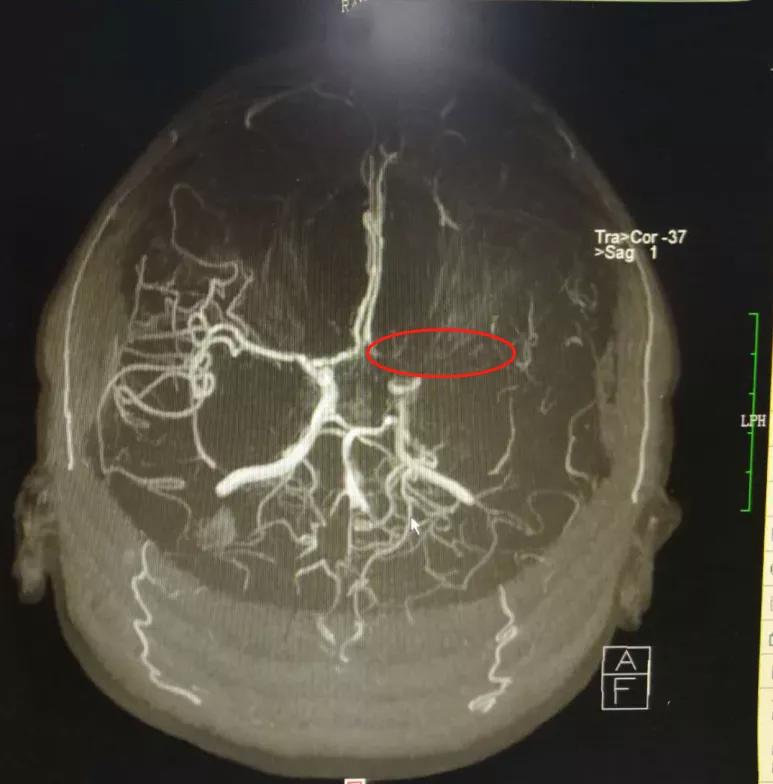

患者做头颈部血管CT(CTA)、数字减影全脑血管造影(DSA)检查,确认颅内动脉是否存在重度狭窄;一般需要完善磁共振(MRI)或CT灌注成像(CTP),必要时进行高分辨核磁共振检查。这些检查结果都要由神经内科医生结合临床进行评估。

术前磁共振血管成像(MRA)提示左侧大脑中动脉闭塞